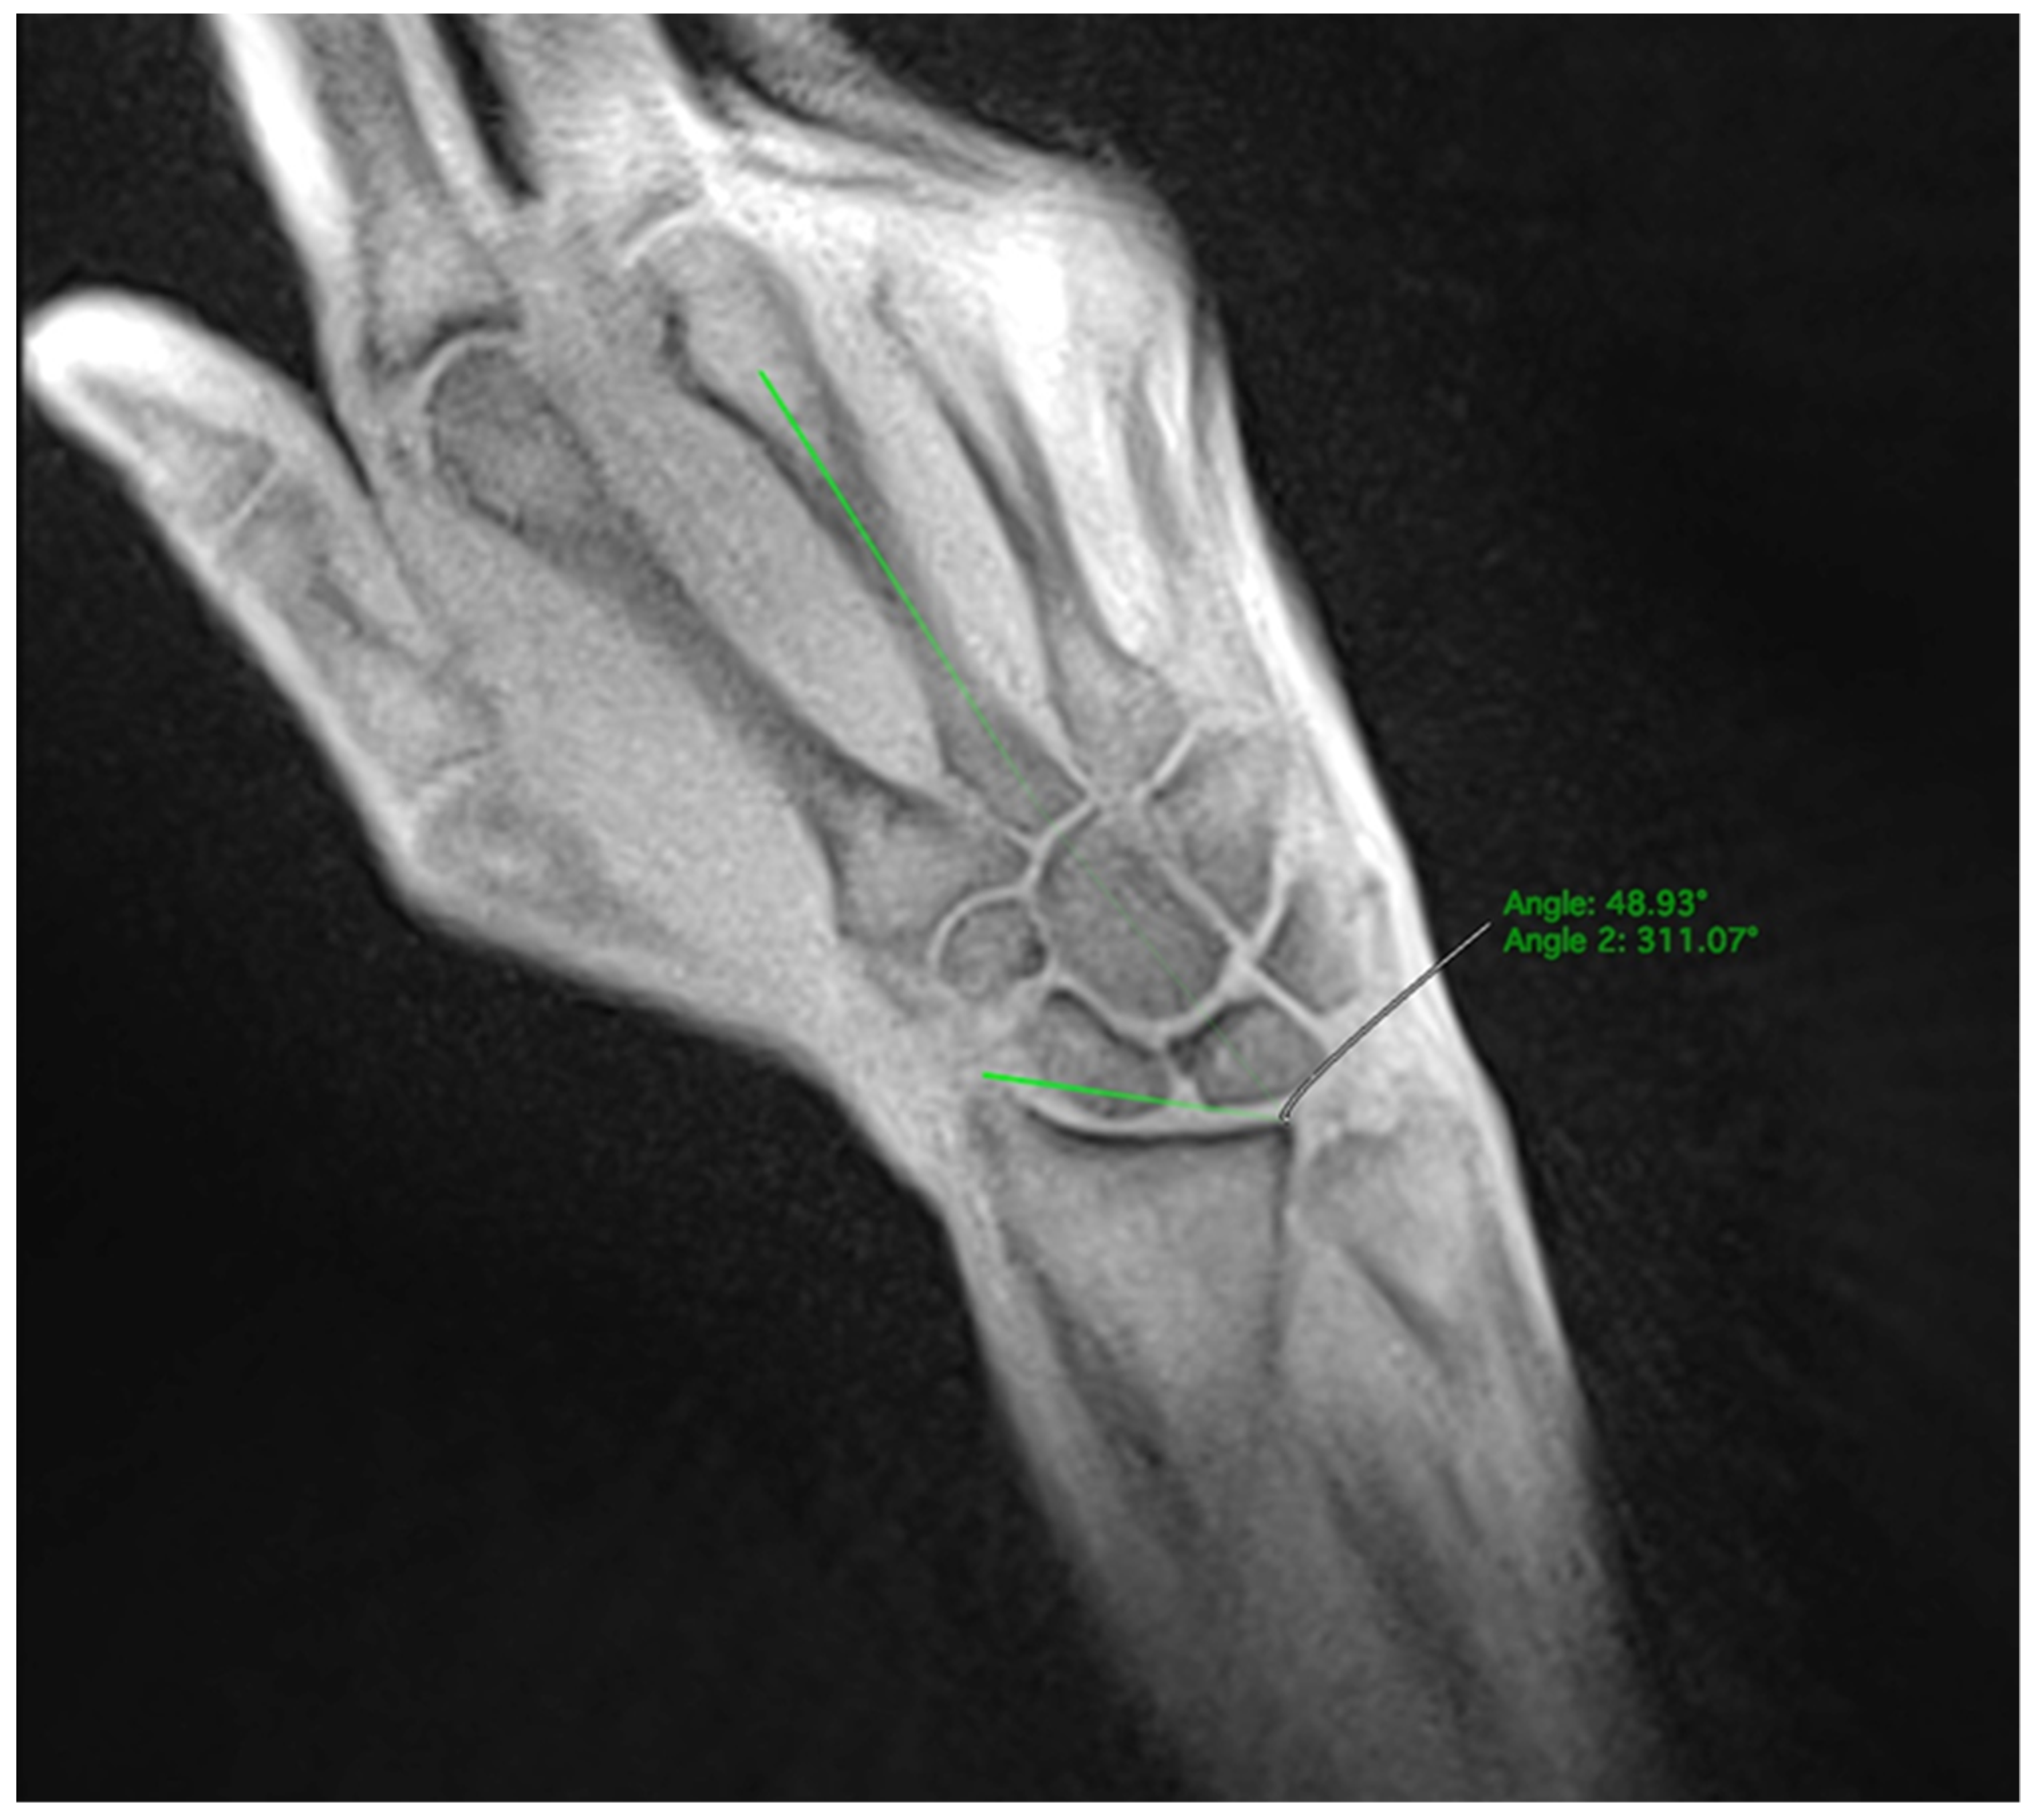

The participants were given commands through headphones to move radially or ulnarly within the previously practiced range of motion at a constant speed. The movement sequence was performed five times with two-minute breaks between each sequence. A subset of participants additionally performed a fist clench maneuver by compressing an elastic ball in a neutral position. During dynamic imaging, a series of 2D images were acquired every 50 milliseconds with an in-plane resolution of 0.75 mm and a slice thickness of 4 mm given a field of view of 192 mm and a matrix of 256 × 256 (Figure 1, Video S1 and S2).

Figure 1. Series of images captured from radial (1) to ulnar deviation (4) during the abduction/adduction maneuver. These images were acquired using a T1-weighted rtMRI sequence with iterative reconstruction, achieving a temporal resolution of 50 ms. Images (14) correspond to frames 156, 207, 226, and 262 out of a total of 300 frames.